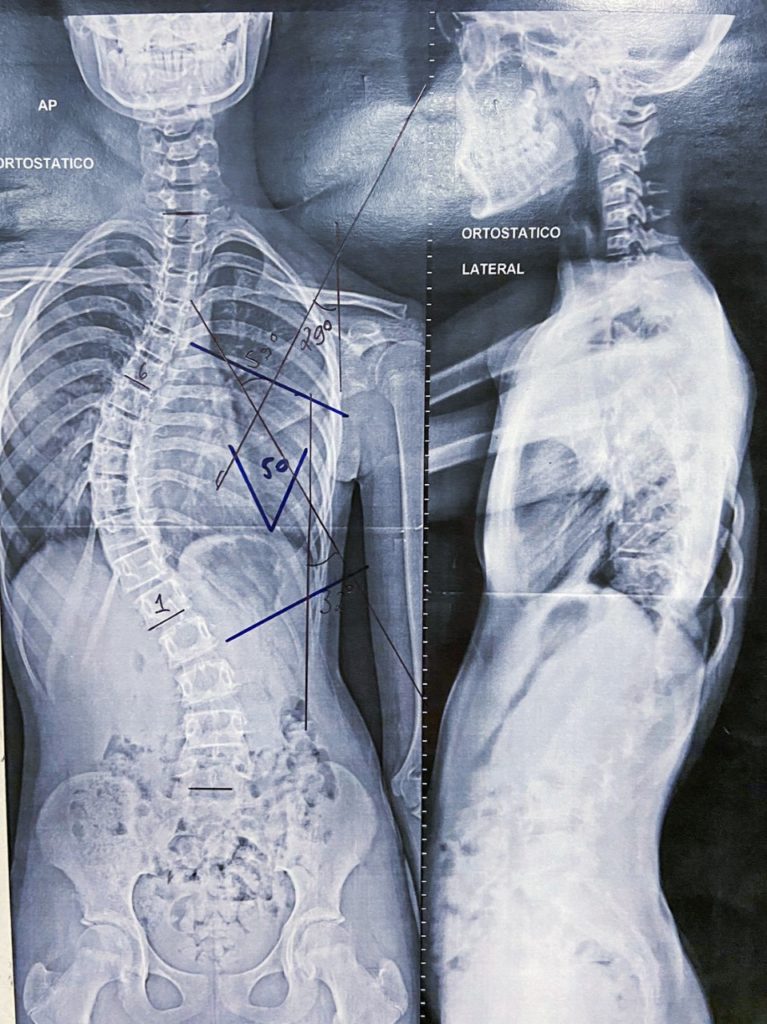

Maria Fernanda, com um quadro grave de escoliose, foi atendida pelo ortopedista Juliano Coelho e já saiu com sua cirurgia marcada.

A escoliose é uma curvatura lateral da coluna vertebral, e em muitos casos, ocorre durante o pico de crescimento pouco antes da puberdade.  A maioria dos casos é leve, com pouco sintomas. Mas em casos graves, que ocorrem à medida que elas crescem, se torna uma deformidade dolorosa.